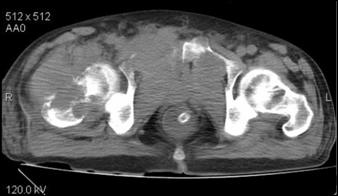

Dupa Wallace (Fig.24 a,b,c,d) [270], dificultati de palpare a unei tumori vezicale pot aparea in urmatoarele situatii :

a) Tumora vezicala de dimensiuni mici. b) Tumora localizata la nivelul domului vezical.

c) Tumora vezicala in trigon. d) Vezica urinara in repletie

Figura 24.